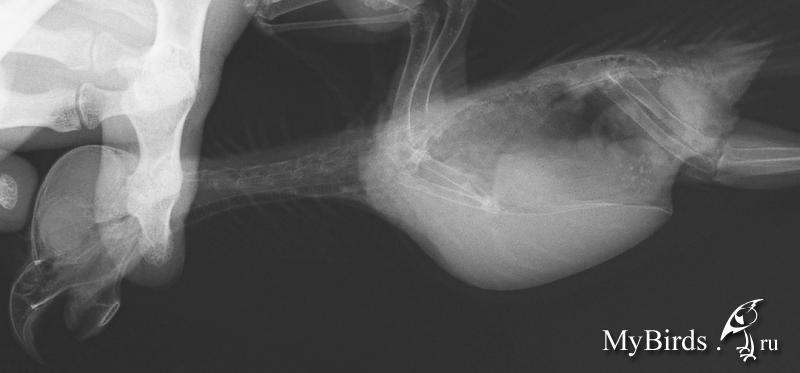

NikaK Опубликовано 9 сентября, 2013 #1 Опубликовано 9 сентября, 2013 (изменено) Розеллы мальчик и предположительно девочкамальчик - 11 лет, девочка год с небольшимрацион содержание и прочее - в темеhttp://www.mybirds.ru/forums/index.php?sho...&hl=розелла сейчас мне нужен только ответ по конкретным рентгенам. большие изображения лежат вот тут ftp://ftp.batteryteam.ru/pdf%20to%20print/Мальчик 11 лет Девочка (может быть нет) 1,5 года вопрос - можно ли по этим снимкам подозревать аспергиллёз?заранее спасибо за ответ. Изменено 9 сентября, 2013 пользователем NikaK

Zosia Опубликовано 9 сентября, 2013 #2 Опубликовано 9 сентября, 2013 У саммца (Жорка,да?) точно что-то есть, и одно легкое нехорошо вздуто. У самки если и есть (в центральной части затемнение)- видно плохо. Анализ нужно делать,причем 3 раза.Аспергиллез по трем анализам ставят,два должно быть положительно. Т.к. лечение его а)- дорогое (очень), б)- токсично, требует параллельно несколько препаратов- для прикрытия.

Zosia Опубликовано 10 сентября, 2013 #10 Опубликовано 10 сентября, 2013 Так.Поговорила с теми,кто вас сейчас ведет. Мое мнение- до аспергиллезного диагноза вам надо исключить ТУБЕРКУЛЕЗ,т.к. ваша упавшая иммунка, и то что на ваших птиц все садится, и то что одна птица явно заразилась от второй (а такого в ДОМАШНИХ условиях при аспергиллезе практически не бывает,зато бывает при туберкулезе) и специфически вздутое лоегкое, и сетчатый рисунок на нем- может говорить именно о Т, а не о А. исключить (или подтвердить) Т легче,чем А. Это сделают в Горветлаборатории.Я созвонилась с ними, и созвонилась в Мариной Лешковой (Центр, вы в четверг илите- будете сдавать кровьЮ смыв и,возможно,фекалии- на исключение туберкулеза. До результатов анализа- максимально птицу иммунить (всем чем можно- от катозала до фоспренила), только если прмиенять будете параллельно два иммуностимулятора- дозы давать половинные по каждому. А иммуномодулятор (деринат например) или иммунопротектор (катозал)- без изменений.Дозы "стандарт" по иммуностимуляторам: 0,02 мл на каждые полные 50 граммов веса птицы суточноИммуномодуляторы- 0,054 мл суточно на каждые 50 граммовиммунопротекторы- 1:200 в поилку.исключить все фрукты и овощи (ВРЕМЕННО).Никаких витаминов.

Zosia Опубликовано 10 сентября, 2013 #12 Опубликовано 10 сентября, 2013 тогда я правильно не начала давать назначенный орунгал Н.С. так там в четверг будет принимать Лешкова? А с Волгиной мне как объясниться?) Точно так же. Наталья Сергеевна сейчас на конференции в НовоСибе, но она будет в курсе. Я могу объяснитьна чем базируется мое мнение(как я М уже объяснила).1. Изначально была нездорова одна птица. Вторая заразилась от неё. При аспергиллезе такого в условиях квартиры или квартирного вольера не происходит (у вас же не капает по стенам,не ползет плесень по углам, не летает гуано и сопли-как на прицефермах). А вот туберкулез вполне воздушно-капельным путем даже в квартирных условиях мог передаться.2.Иммунка у вас упала уже полтора года как. На аспергиллезе птиц бы уже помер.На туберкулезе может жить долго- если постоянно поддерживать антибиотиками (даже непрофильными),иммуностимуляторами.3.У самца резко вздуто одно легкое- по клинике детей это характерно для туберкулеза. Хотя А тоже может такое дать(агрессивный), но опять же- птиц бы уже ушел за радугу.4.Мозаичный рисунок легких... 5.У самки по центру что-то.похожее на аспергилломы, виднеется.Но ровно так же это может быть и туберкулемы. Ответ даст только анализ. На анализ будет взята кровь,мазок,помет.Проводить будут в Горветлаборатории (ул.Юннатов 16 а), я с ними созвонилась уже. В принципе можно было бы обойтисьь гораздо меньшими проблемами, если бы была туберкулиновая проба.НО! Нет сейчас в Москве малых фасовок птичьего пробника,только по 38 кг (на птицефермах), а отщипнуть не дают. А так- можно было бы поцарапать кожу,нанести пробу и посмотреть результат. Хотя конечно бывают наверное какие-то варианты аспергилл, нетипичные, малоагрессивные, при этом высокоустойчивые к внешним факторам и передающиеся прямо по сухому воздуху московских квартир (26,30% влажности в отопительный сезон). Как известно,только гильотина дает 100% однозначный результат.если будет туб- его лечить уже чисто антибиотиками.с прикрытием системными антмикотиками. лечат долго, но хоть уверенно.

NikaK Опубликовано 12 сентября, 2013 Автор #18 Опубликовано 12 сентября, 2013 (изменено) Так, была на приеме, взяли кровь, дали две пробирки для помета. Но...позвонита в горвет на юннатов - они сказали, что:1. анализ ТАКОЙ можно сдавать ТОЛЬКО при направление наблюдающего врача...они конечно не откажут взять, но типа это на них вешается ответственность лишняя, и им это не очень то хочется. сказали под паспортные данные - ок, фиг с ними.2. КРОВЬ - НЕ берут на туберкулез... берут смыв из глотки, помет, и что-то еше, я от удивления забыла. Получается что у меня только 1 из 3 анализов... достоверность видимо равна ....и еще посмотрели еще пристально Н.С. и Мария рентген обоих - приказывают лечить орунгалом (+ преднизолон для триши с полиурией, +пробиотик, +АЦЦ в поилку, +мовалис 2 недели, + иммунофан для обоих все кроме 1) ... я еще больше в растерянности... Изменено 12 сентября, 2013 пользователем NikaK

Zosia Опубликовано 15 сентября, 2013 #31 Опубликовано 15 сентября, 2013 сегодня второй день по вышеописанной схеме - ттт! - все вроде без проишествий... надеюсь и дальше так же будет. а аспергиллез- -так же, ничем 100% не подтверждается у живой птицы? Подтверждается, но не всегда.Кишечный- легко,легочный- очень трудно. Рентгеноскопически- при наличии аспергиллом явных (тут как раз обязательно дифференциировать от тубекулеза,т.к. он дает туберкуломы,похожие немного на аспергилломы).Вздутые легкие и мешки,наличие жидкости в них,тяжелое и мелкое дыхание, ослабленность,упавшая иммунка.Т.е. часть симптомов- косвенная и может быть неоднозначна.(Микоплазмоз напрмиер,который у вас исключали в первую очередь).